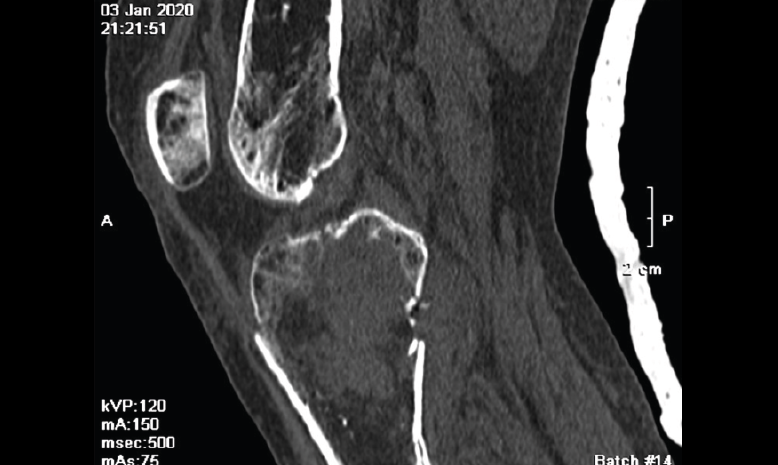

5.1. TA-GT (tuberosidad tibial anterior-garganta de la tróclea)

En pacientes sintomáticos con inestabilidad rotuliana, la TAC es útil para medir la TA-GT(10). La distancia TA-TG es una medida radiológica propuesta por Goutallier y Bernageau que sirve para cuantificar el ángulo Q. Consiste en medir la distancia en milímetros de la tuberosidad tibial anterior a la garganta de la tróclea proyectadas sobre una línea que pasa por los bordes posteriores de ambos cóndilos femorales, superponiendo 2 cortes axiales de TAC. Es una medida fiable y reproducible pero poco precisa, con un margen de error de más de 4 mm. La distancia TA-GT es mayor de 20 mm en el 56% de las inestabilidades rotulianas y tan solo en el 3% de la población sana(11) (Figura 28).

5.2. Balance rotuliano

Mide la inclinación de la rótula en relación con el borde posterior de los cóndilos femorales (Figura 29).

Figura 28. Corte axial de tomografía axial computarizada con superposición de imágenes con rótula y parte posterior de cóndilos y tuberosidad tibial anterior, que nos permite medir la distancia TA-GT, en condiciones normales hasta 2 cm.

Figura 29. Corte axial de tomografía axial computarizada con superposición de imágenes con rótula y parte posterior de cóndilos y tuberosidad tibial anterior, que nos permite medir el tilt o balance rotuliano, en condiciones normales hasta 20°.